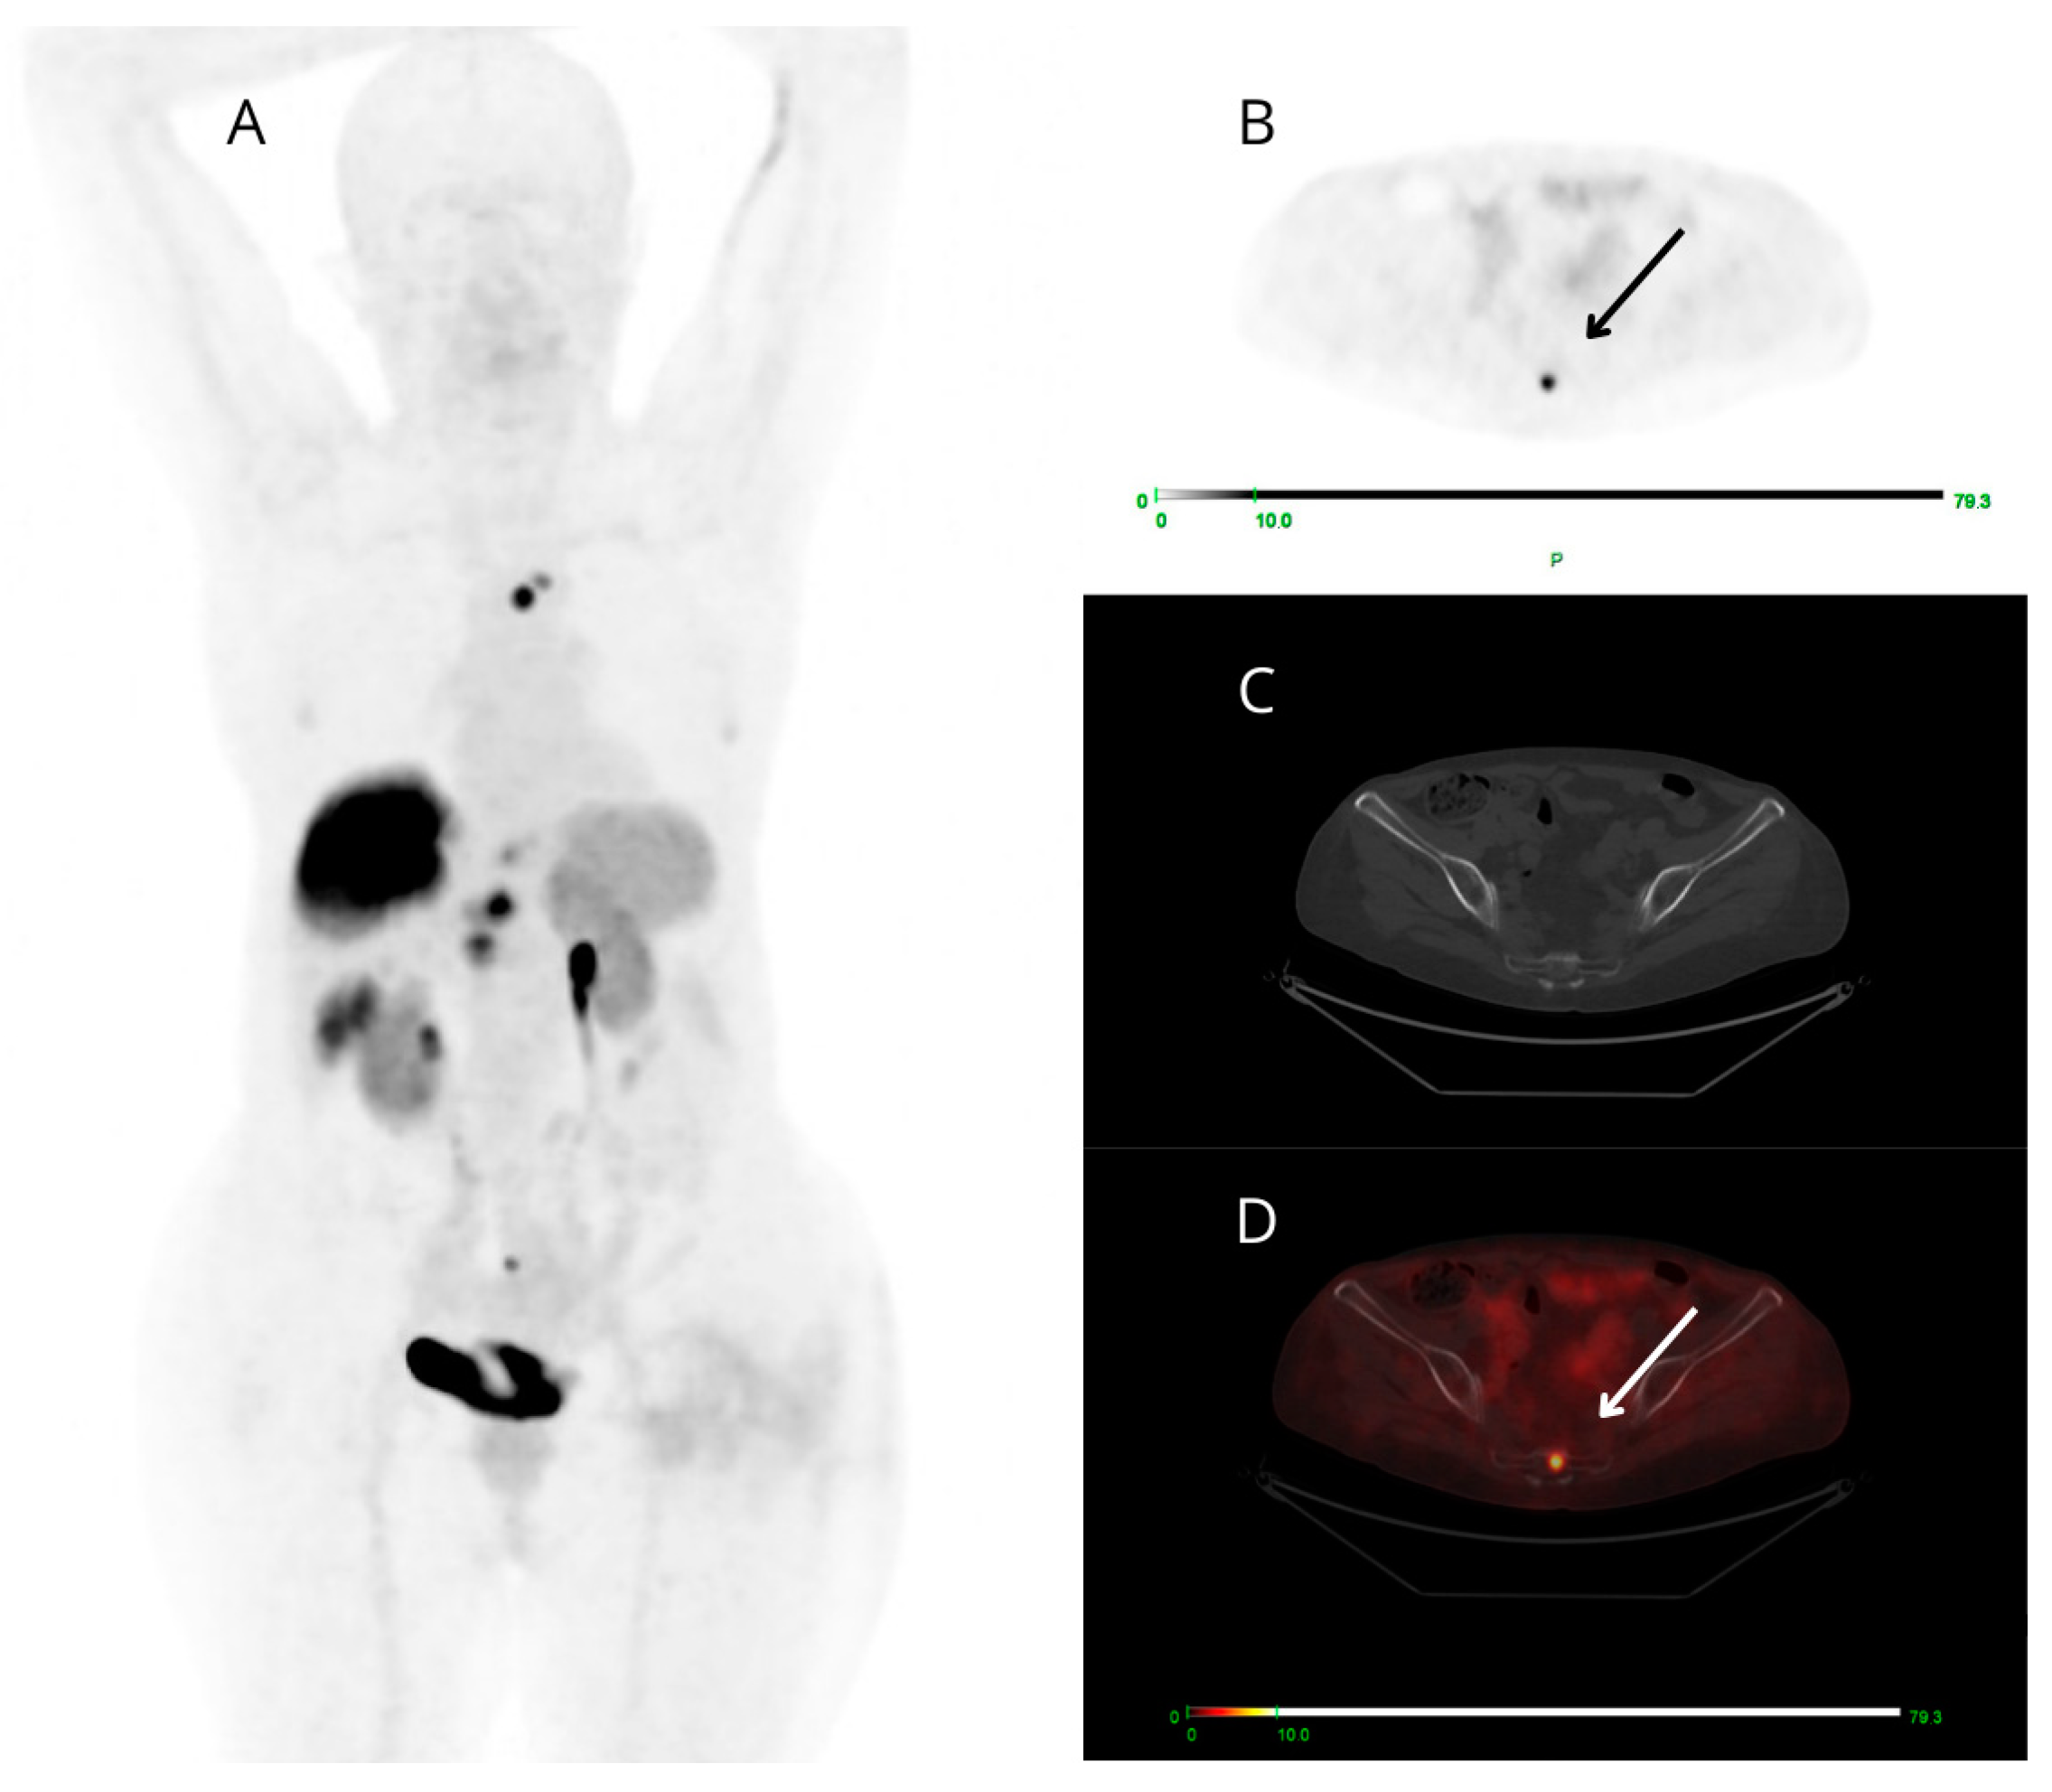

Among the 13 PET-positive targeted small findings (all true positive), 6/13 cases presented ceCT-negative small lesions (at bone level in 4/6 patients and node level in 2/6 cases) (Figure 4), 2/13 showed both small-sized PET-positive lesions (false negative on ceCT) and additional small-sized lesions reported as indeterminate on ceCT that were not detectable on PET/CT. There was also a small group of only 5/13 patients presenting both concordant and discordant PET-positive findings: each case presented a target PET-positive small finding confirmed by ceCT (concordant true positive) and a small finding clearly avid on PET images (2 pancreatic, 2 nodal and 1 at soft tissue level), known as malignant at ceCT only after expert radiological revision, aware of the PET result.

Figure 4.

Maximum intensity projection (MIP) (A), PET (B), CT (C), and fused PET/CT (D) transaxial images of a patient studied for restaging of metastatic G3 NET, likely of pancreatic origin. [68Ga]Ga-DOTANOC PET shows high and focal uptake at the coccyx (arrows). The uptake area does not correspond to clear morphologic alterations on low-dose CT.